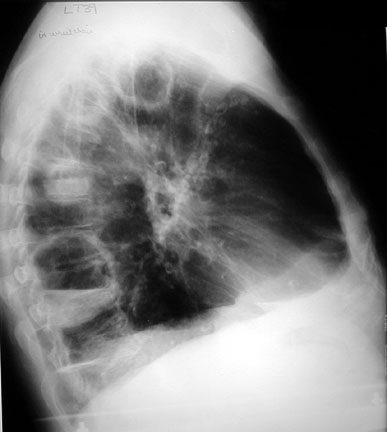

weekly clinical round for undergraduate from 8 to 11 AM during which interpretation of CHEST X rays was done for all cases of cardiothoracic surgery, gived by 2 staf member for 3 months